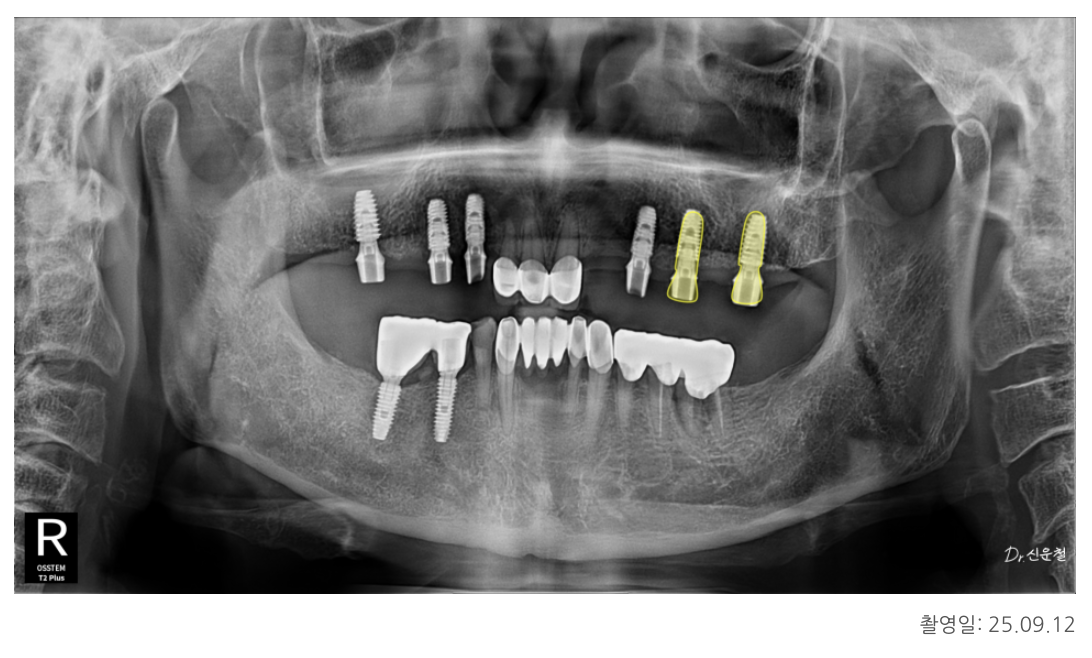

5개 상실 → 안정된 3개로 복원

왼쪽은 앞쪽부터 뒤쪽까지 총 5개가 빠져 있었습니다.

한 줄 길게 만들면

양 끝에서 서로 잡아당기는 힘 때문에 오래 버티기 힘들기 때문에

오른쪽과 동일하게

✔ 튼튼한 두 곳에만 임플란트 식립

✔ 그 사이 치아는 자연스럽게 연결하여 3개 회복

했습니다.

치료 결과

환자분은 치료 후

“이제 어느 쪽으로 씹어도 편하다” 고 가장 먼저 말씀하셨습니다.

전체적인 치아 복원에서 중요한 것은

치아를 얼마나 많이 만들었는가가 아니라,

“어디에 심어야 오래 버티는 구조가 되는가” 입니다.